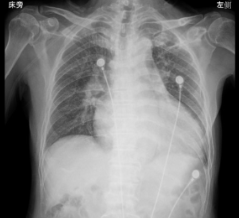

患者X线下扩大的心脏。

72岁的张魁北(化名)6年前开始出现活动后气促,最初爬楼梯费力,后来连走路都气喘吁吁,就医后诊断为“扩张型心肌病、心衰、高血压病”。6年中他反复住院,病情逐渐恶化,甚至睡觉翻身、上厕所都会呼吸困难,生活质量一落千丈。此次入院,心脏超声显示他的心脏已像吹胀的气球(左心室直径达89mm,正常男性≤55mm),射血分数仅11%(正常人≥55%),被确诊为扩张型心肌病、重度心衰。